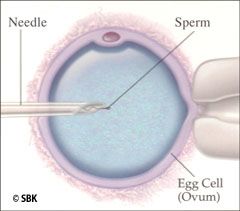

Paso 3: Extracción del Huevo: El doctor aspira cada folículo maduro con una aguja guiada por ultrasonido. El procedimiento se lleva con sedación administrada por un anestesiólogo matriculado y en una sala especial de extracción de huevos con filtración de aire. Esto generalmente se realiza a través de la parte posterior de la pared vaginal pero en ocasiones raras, puede llevarse a cabo por el abdomen. Los huevos aspirados luego se transfieren al embriólogo para que realice la identificación y fertilización.

Paso 3: Extracción del Huevo: El doctor aspira cada folículo maduro con una aguja guiada por ultrasonido. El procedimiento se lleva con sedación administrada por un anestesiólogo matriculado y en una sala especial de extracción de huevos con filtración de aire. Esto generalmente se realiza a través de la parte posterior de la pared vaginal pero en ocasiones raras, puede llevarse a cabo por el abdomen. Los huevos aspirados luego se transfieren al embriólogo para que realice la identificación y fertilización.

Esta es la etapa en la cual la micromanipulación adicional puede ocurrir si así fuera necesario, como por ejemplo la ICSI. En el ICSI, un embriólogo inyecta un solo espermatozoide directamente en un huevo maduro bajo microscopio. Este procedimiento se realiza para aumentar la probabilidad de fertilización cuando existe un problema en el factor masculino como por ejemplo un conteo de espermatozoides bajo, motilidad o morfología pobre, o cuando las técnicas de aspiración de los espermatozoides TESA ó MESA se utilizan para obtener una muestra de espermatozoides. La ICSI también se recomienda si la fertilización no ocurrió en intentos previos de fertilización in vitro.

Esta es la etapa en la cual la micromanipulación adicional puede ocurrir si así fuera necesario, como por ejemplo la ICSI. En el ICSI, un embriólogo inyecta un solo espermatozoide directamente en un huevo maduro bajo microscopio. Este procedimiento se realiza para aumentar la probabilidad de fertilización cuando existe un problema en el factor masculino como por ejemplo un conteo de espermatozoides bajo, motilidad o morfología pobre, o cuando las técnicas de aspiración de los espermatozoides TESA ó MESA se utilizan para obtener una muestra de espermatozoides. La ICSI también se recomienda si la fertilización no ocurrió en intentos previos de fertilización in vitro.

La ICSI ha representado uno de los mayores adelantos en el tratamiento de la infertilidad por factor masculino. La ICSI consiste en la inyección de un solo espermatozoide en un óvulo (huevo) maduro. En este procedimiento un embriólogo manipula, bajo microscopio, un huevo maduro extraído mientras inyecta una microaguja cargada con un solo espermatozoide directamente en el huevo maduro. Este adelanto, en manos de un embriólogo experto, puede aumentar la probabilidad de fertilización hasta un 85 por ciento. El procedimiento de ICSI está indicado en parejas con: